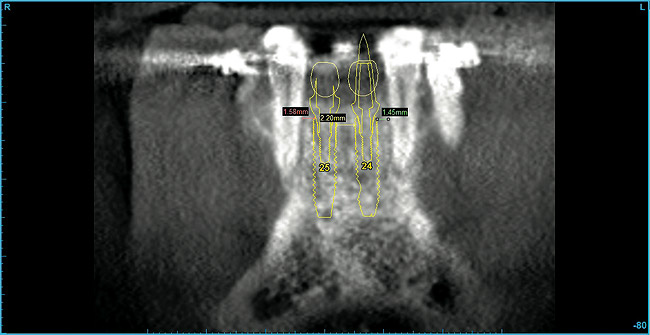

From a surgical perspective, the highest priority is the protection of vital anatomic structures from the trauma of surgery. When performing implant placement in the posterior mandible, it is critical to avoid trauma to the inferior alveolar neurovascular bundle (inferior alveolar canal) and prevent perforation of the lingual cortex. In a radiographic study, evaluating human CT scans, Quirynen et al reported on the variations of mandibular anatomy 4 mm to 6 mm anterior to the mental foramen.1 These authors introduced three classifications, based on the geometry of the mandibular bone and presence of lingual concavities and inclinations. Knowledge of the local anatomic situations in proposed implant sites can prevent potentially catastrophic injury during implant insertion. A CT scan affords the surgeon the opportunity to measure and appreciate the locations of these structures, but not the vertical and horizontal drill control necessary to be absolutely certain that inadvertent over-preparation or deviations do not occur. Many manufacturers sell so-called "drill stops," but these offer little horizontal control in softer bone types. The fabrication of a surgical guide, stabilized by either teeth or fixed via fixation screws onto the surrounding alveolar ridge or mucosa, affords the surgeon an opportunity to perform surgery based on planning software and a "sleeve-in-sleeve" system to control horizontal and vertical limits of the twist drills used for osteotomy preparation. Using this concept, Horowitz et al2 demonstrated small angular and vertical deviations from planned implant positions in vitro. This is demonstrated by the first clinical example. A cone-beam CT scan allows the surgeon to locate the 3-dimensional location of the IAC and lingual concavity of the mandibular alveolus (Figure 1 and Figure 2). Next, implant positions based on the prosthetic treatment plan and translated to the scan via a barium-containing scanning appliance (Figure 3), are planned via various planning software. Sarment et al3 compared the accuracy of implant placement between a "standard" surgical guide and a stereolithic guide by comparing the spatial deviations between virtual and actual placement in mandibular models. The control guide resulted in coronal deviations of 1.5 mm +/- 0.7 mm and 2.1 mm +/- 0.97 mm at the apical end. The use of the stereolithic guide produced coronal deviations of 0.9 mm +/- 0.5 mm and apical deviations of 1 mm +/- 0.6 mm. The authors concluded that this type of surgical guide can improve the accuracy of implant placement. In a study evaluating the accuracy of implant placement using an integrated system of guidance, Dreiseidler4 found crestal deviations of 217 µm +/- 99 µm and apical deviations of 343 µm +/- 146 µm when comparing planned and actual placements on a partially edentulous model. They also reported on an axial deviation of 1.09° +/-0.51°.

Figure 1  A cone-beam CT scan allows the surgeon to locate the 3-dimensional location of the IAC and lingual concavity of the mandibular alveolus.

Figure 1

Figure 2  Lingual concavity visualized.

Figure 2